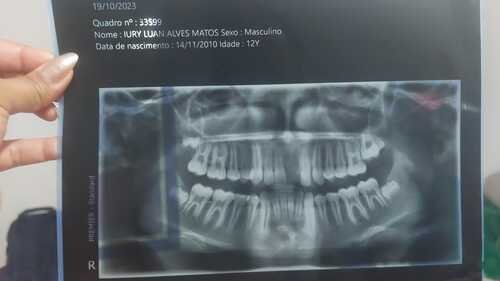

Meu nome é Alexandra, criei essa vaquinha porque preciso arrecadar R$ 2.300,00 para realizar o tratamento dentário do meu sobrinho Iury Luan Alves Mato, nascido em 14/11/2010.No dia 17/10/2023, ele foi atropelado por um motoqueiro à caminho da escola, o mesmo negou socorro e não era habilitado. Iury sofreu algumas lesões no corpo e também perdeu o dente da frente e teve algumas trincas nos demais dentes! Agradecemos a Deus pela vida dele e agradeço a Deus pela vida de cada um de vocês. No entanto, esse acontecimento tem mexido muito com o emocional dele, está com vergonha de retornar para escola, não sorrir mais, vejo que o emocional dele está muito abalado. Peço humildemente que possam nos ajudar, e devolver ao Iury seu sorriso e a alta estima. Muito obrigada!